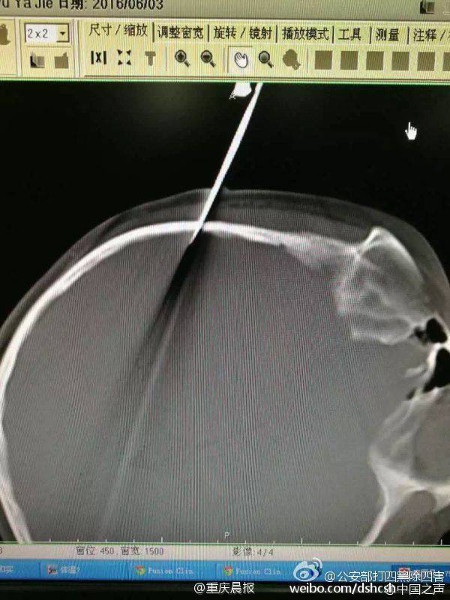

Mới đây, một vụ tai nạn nghiêm trọng đã xảy ra tại Thượng Hải, Trung Quốc khi một ông bố trong lúc nóng giận đã cầm kéo phi vào đầu con gái 10 tuổi của mình. Chiếc kéo đã cắm xuyên qua đầu cô bé đến tận vùng não.

Bé gái bị cha phi kéo cắm xuyên vào tận não.

Ngay sau vụ việc, cô bé đã được đưa ngay tới bệnh viện để cấp cứu. Các bác sĩ tiến hành phẫu thuật để rút chiếc kéo dài 15cm ra khỏi phần xương sọ của cô bé. Hiện tại, tình hình sức khỏe của bé gái đã khá hơn, mặc dù cô không thể nhớ chuyện gì đã xảy ra.

Ảnh chụp cắt lớp não và chiếc kéo.